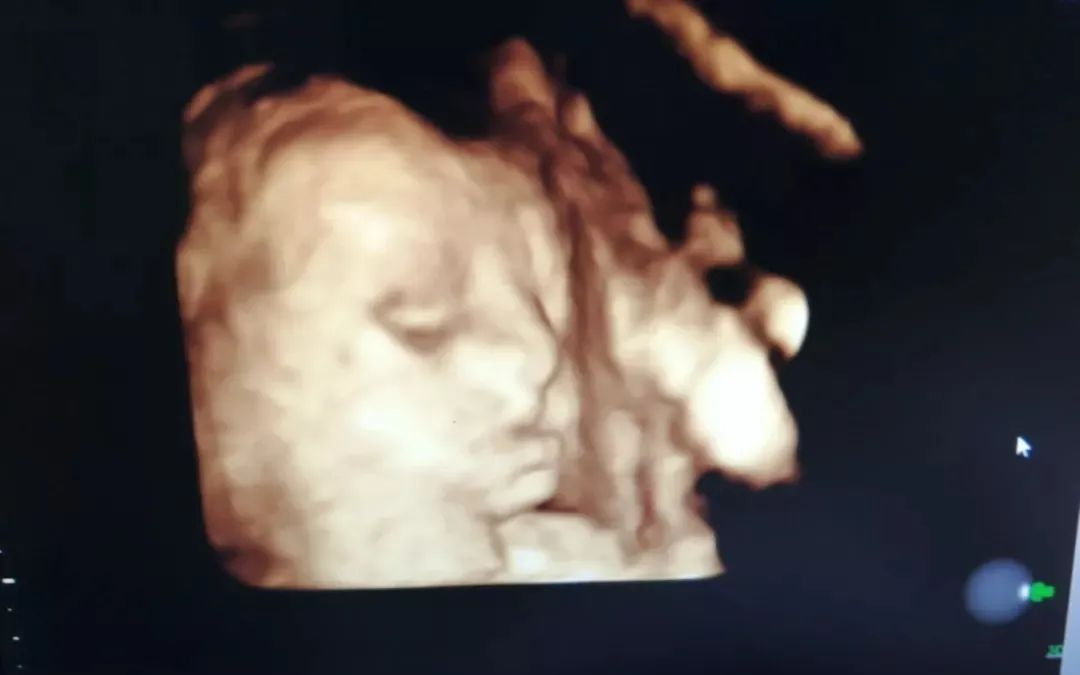

四维彩超可以直观、立体显示人体器官的三维结构及动态,实时地观察立体结构,所以准妈妈们还可以看到胎儿在母体内微笑、咬手、踢腿、伸懒腰、打哈欠的调皮可爱模样。